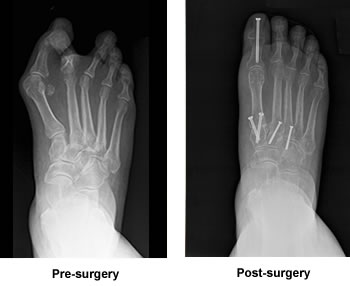

Surgery Avoids Hammertoe Amputation

In January 2013, I saw a podiatrist who spoke of amputating my hammer toe. Lucky for me a close friend implored me to see Dr. Leavitt.

On May 8, 2014, I drove to surgery knowing that I wouldn't be in that seat for at least 3 months. On July 8, I was cast free. I held my breath as Dr. Leavitt said, "You know what? You are 100% healed!" I just stared at my beautiful straight-toed foot. I do this often as I am in awe of what it is now.